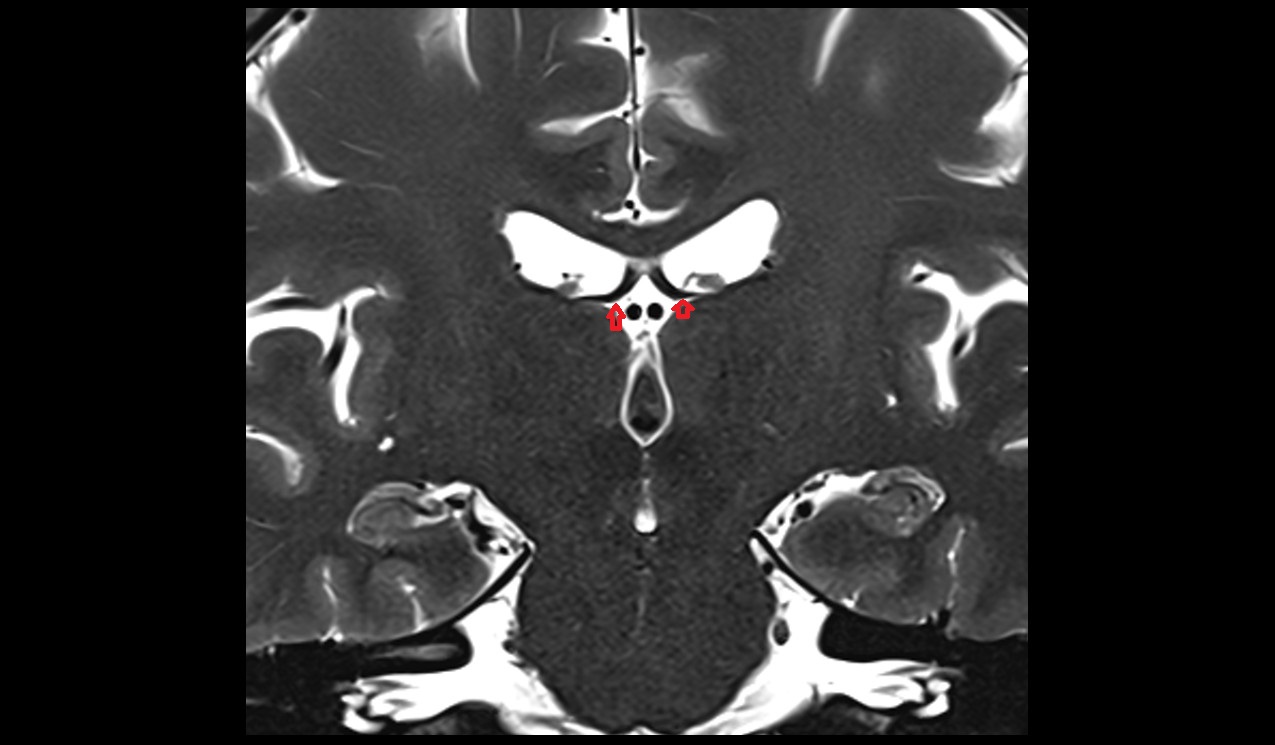

- Abducens nerve (Cranial nerve VI)

- Nucleus of abducens nerve